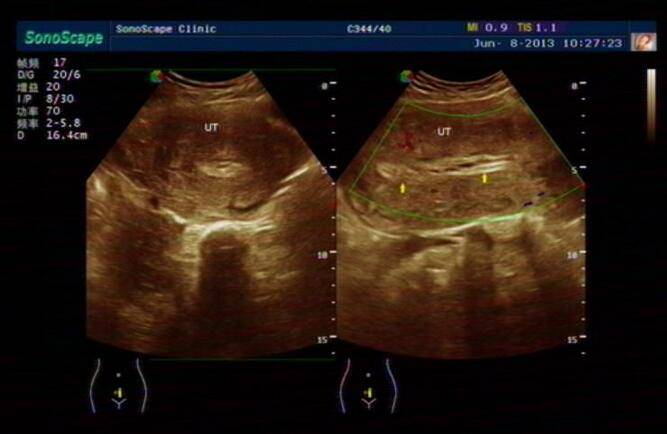

◆纵隔子宫

两侧副中肾管已全部会合,但纵隔未退化,子宫外形正常,宫腔被隔成两部分。如果纵隔末全退化,则形成不全纵隔子宫。如果纵隔延伸至阴道,则可同时形成阴道纵隔。纵隔子宫仅有一个输卵管与卵巢,多数生育能力低下,少数人可怀孕,但易造成流产及产科并发症。